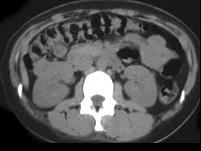

问题 男,58岁,无痛性肉眼血尿1个月余,请结合CT图像作出诊断 ( )

选项 A、右肾血管平滑肌脂肪瘤 B、右肾黄色肉芽肿性肾盂肾炎 C、右侧囊性肾癌 D、右肾结核性肉芽肿 E、右侧肾癌

答案 E